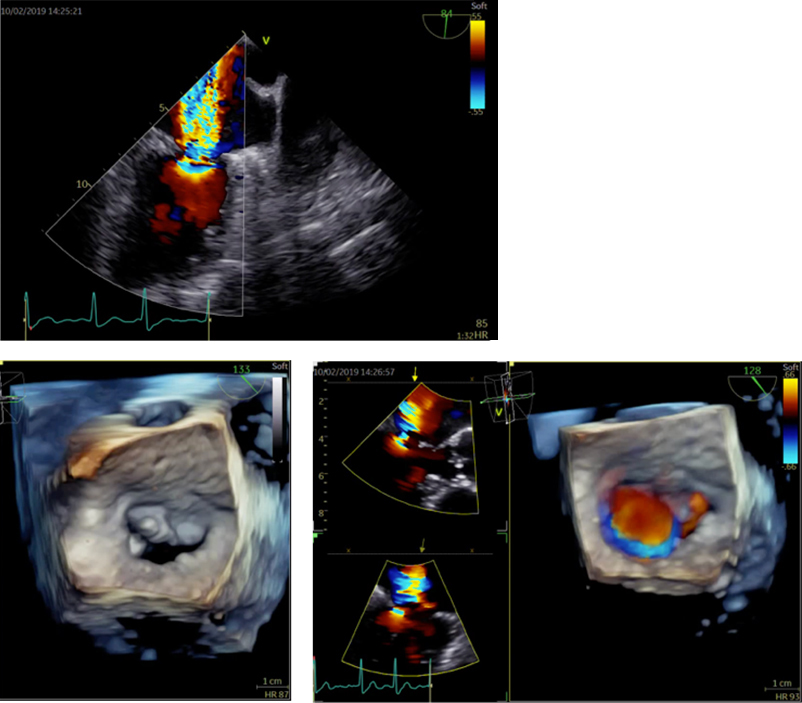

経食道心エコー検査

経食道心エコーは胃カメラとよく似た検査ですが、胃を見るわけではありません。胃カメラと同じような長い管を飲み込んでいただき、超音波を使って食道からすぐ隣の心臓の中を詳細に観察する検査です。心臓の中の構造やサイズが非常に細かくわかるので、この検査でなければ診断がつかない疾患もあります。3D技術がもっとも威力を発揮する検査です。

当院では静脈麻酔を用い、軽く眠っている間に検査を行いますので苦痛はほとんどありません。検査を行うのは医師で、看護師が付き添います。

所要時間は麻酔も合わせて30分〜40分程度です。